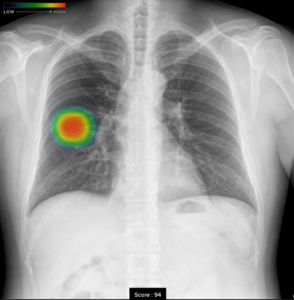

本特徴としましては、AI技術を活用して胸部単純X線画像から結節・腫瘤影、浸潤影、気胸の3つの画像所見を検出し医師の画像診断を支援するものです。

撮影した胸部単純X線画像を自動解析し、結節・腫瘤影、浸潤影、気胸が疑われる領域を検出しマーキングします。

結節・腫瘤影